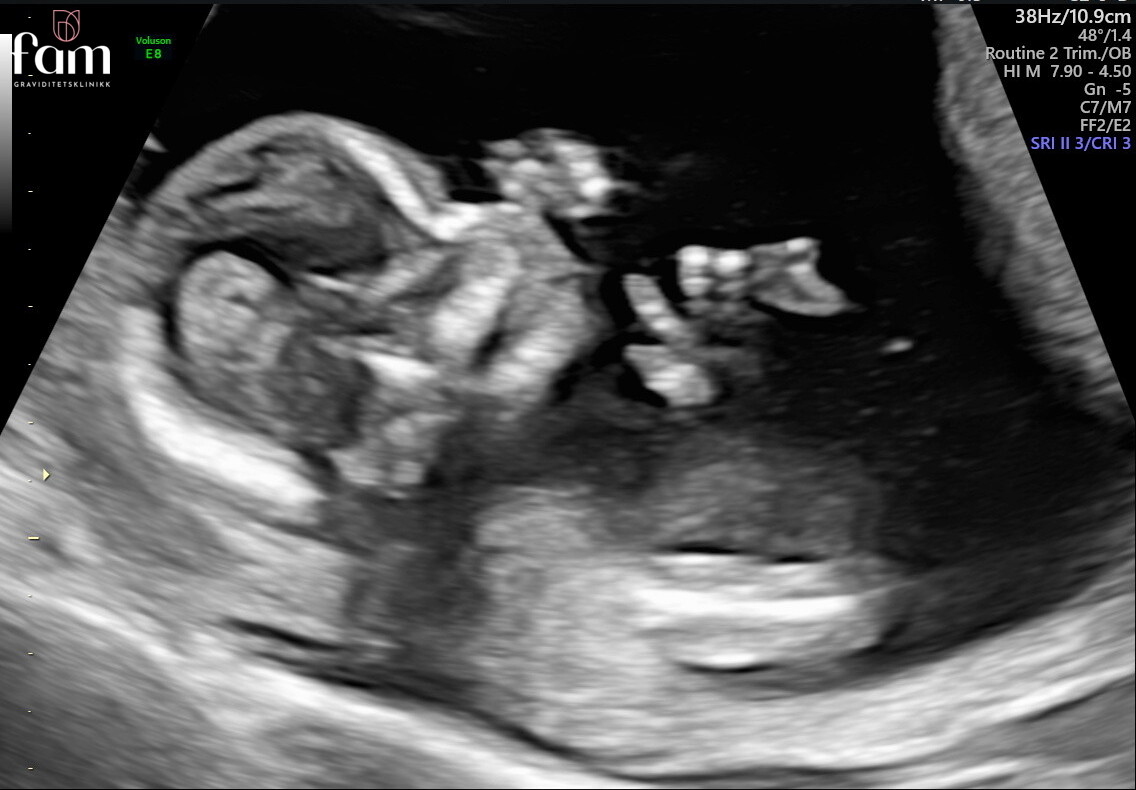

Vi var på privat UL for å finne ut av kjønnet i dag, for jeg har vært så spent! Har ikke fått innkalling til OUL ennå, så har vært ekstra utålmodig på en UL :hilarious:

Alt sto bra til med lille i magen, og det er visst ei lita jente inni der :love017:Heartpink Det er veldig stas ❤️ Det er sååå mange søte kjoler og klær med volanger og sløyfer, så jeg gleder meg til å dulle litt med henne, noe lommeboka ikke kommer til å like :hilarious:

Men alt så bra ut på UL, og hun lå og svelget masse fostervann og vinket til oss :love017